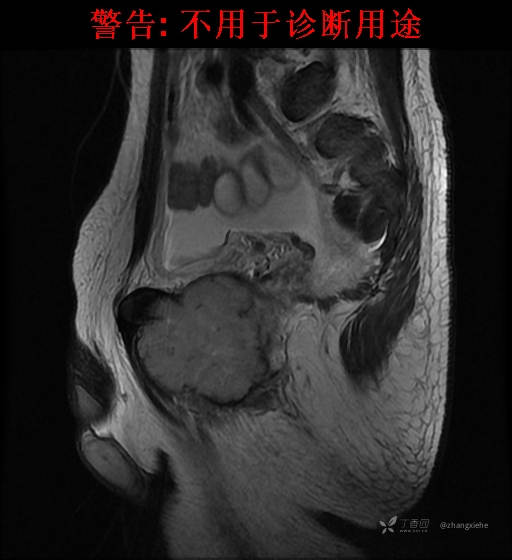

现病史:患者2022-02-07在市中医院体检发现右肺占位,胸部CT示:右肺下叶基底段见一不规则软组织密度影,增强扫描呈轻中度强化,可见血管贴边征。当时无任何不适。2022-02-24于省肿瘤医院行纤支镜检查阴性,痰检未找到癌细胞。经皮肺穿刺细胞学检查找到高度癌疑细胞,病理示:右下肺穿刺考虑神经内分泌癌。免疫组化结果:CgA(-)、CD56(-)、Syn(+)、CK广谱(-)、p40(-)、P63(少量+)、TTF-1(-)、Ki-67(+,40%)、NapsinA(-)、Calcitonin(-)、TG(-)。ECT示:全身骨扫描未见明确骨转移征象。患者出现贫血且逐渐加重、低蛋白血症,予人促红素注射液、精蛋白重组人胰岛素混合注射液、人血白蛋白对症处理,效果不明显,病情加重,右髋出现疼痛,不能行走。2022-03-04转院南大二附院进一步治疗,2022-03-20行右侧髂骨穿刺活检术,术后病理结果示:考虑软组织透明细胞肉瘤。免疫组化示:瘤细胞Vim(+)、NSE(+)、S-100(+)、SOX10弱(+)、Melan-A(+)、TFE-3部分弱(+)、CK(-)、MyoD1(-)、Desmin(-)、HMB45(-)、CD34(-)、CD68(-)、CR(-)、Ki-67约15%(+)。特殊染色示:网状纤维染色(-)、PAS(±)。

2022-03-05血常规示:血红蛋白:64g/L,生化示:白蛋白20g/L。骨髓涂片细胞学检查示:骨髓增生明显活跃,粒红比减低。粒、红、巨三系增生明显活跃。粒系伴成熟障碍。髓片浆细胞较易见,占7%。粒系增生明显活跃,核明显左移,可见巨幼样变及核浆发育不平衡。PET-CT示:1.右肺下叶软组织肿块、右侧耻骨下支及耻骨联合处骨质破坏伴软组织肿块形成,FDG代谢均异常增改,考虑恶性病变,建议病理检查;右侧髂血管旁、双侧腹股沟淋巴结反应性增生,建议随访。2.多浆膜腔(双侧胸腔、心包腔、盆腔)少量积液。3.全身骨骼FDG代谢弥漫增高,考虑骨髓反应性增生。4.大小肠条片状FDG代谢增高,考虑生理性摄取。5.右侧上颌窦面膜下囊肿,脑部FDG代谢未见明显异常。6.C7-T1层面后纵韧带钙化。患者乏力加重,卧床不起,不能承重,大小便不顺畅,转院至我院。门诊拟“1.右肺占位并右侧骨盆转移2.低蛋白血症3.中度贫血 4,血糖升高(原因待查)”收入住院。患者发病以来,无胸闷、胸痛,无呼吸困难,偶咳嗽,无咳血,饮食、睡眠欠佳,2个月之内体重减轻约10kg。

右骨盆及双下肢未见畸形,皮温正常,无浅静脉怒张,右腹股沟中点可触及一质韧肿物,大小约6cm*4cm*5cm,边界不清,固定、压痛明显,叩击痛阳性。右髋关节外旋、屈曲受限。右髋4字试验阳性,左侧阴性,双下肢直腿抬高试验阴性。感觉、运动正常,末梢血运良好,生理反射存在,病理反射未引出。